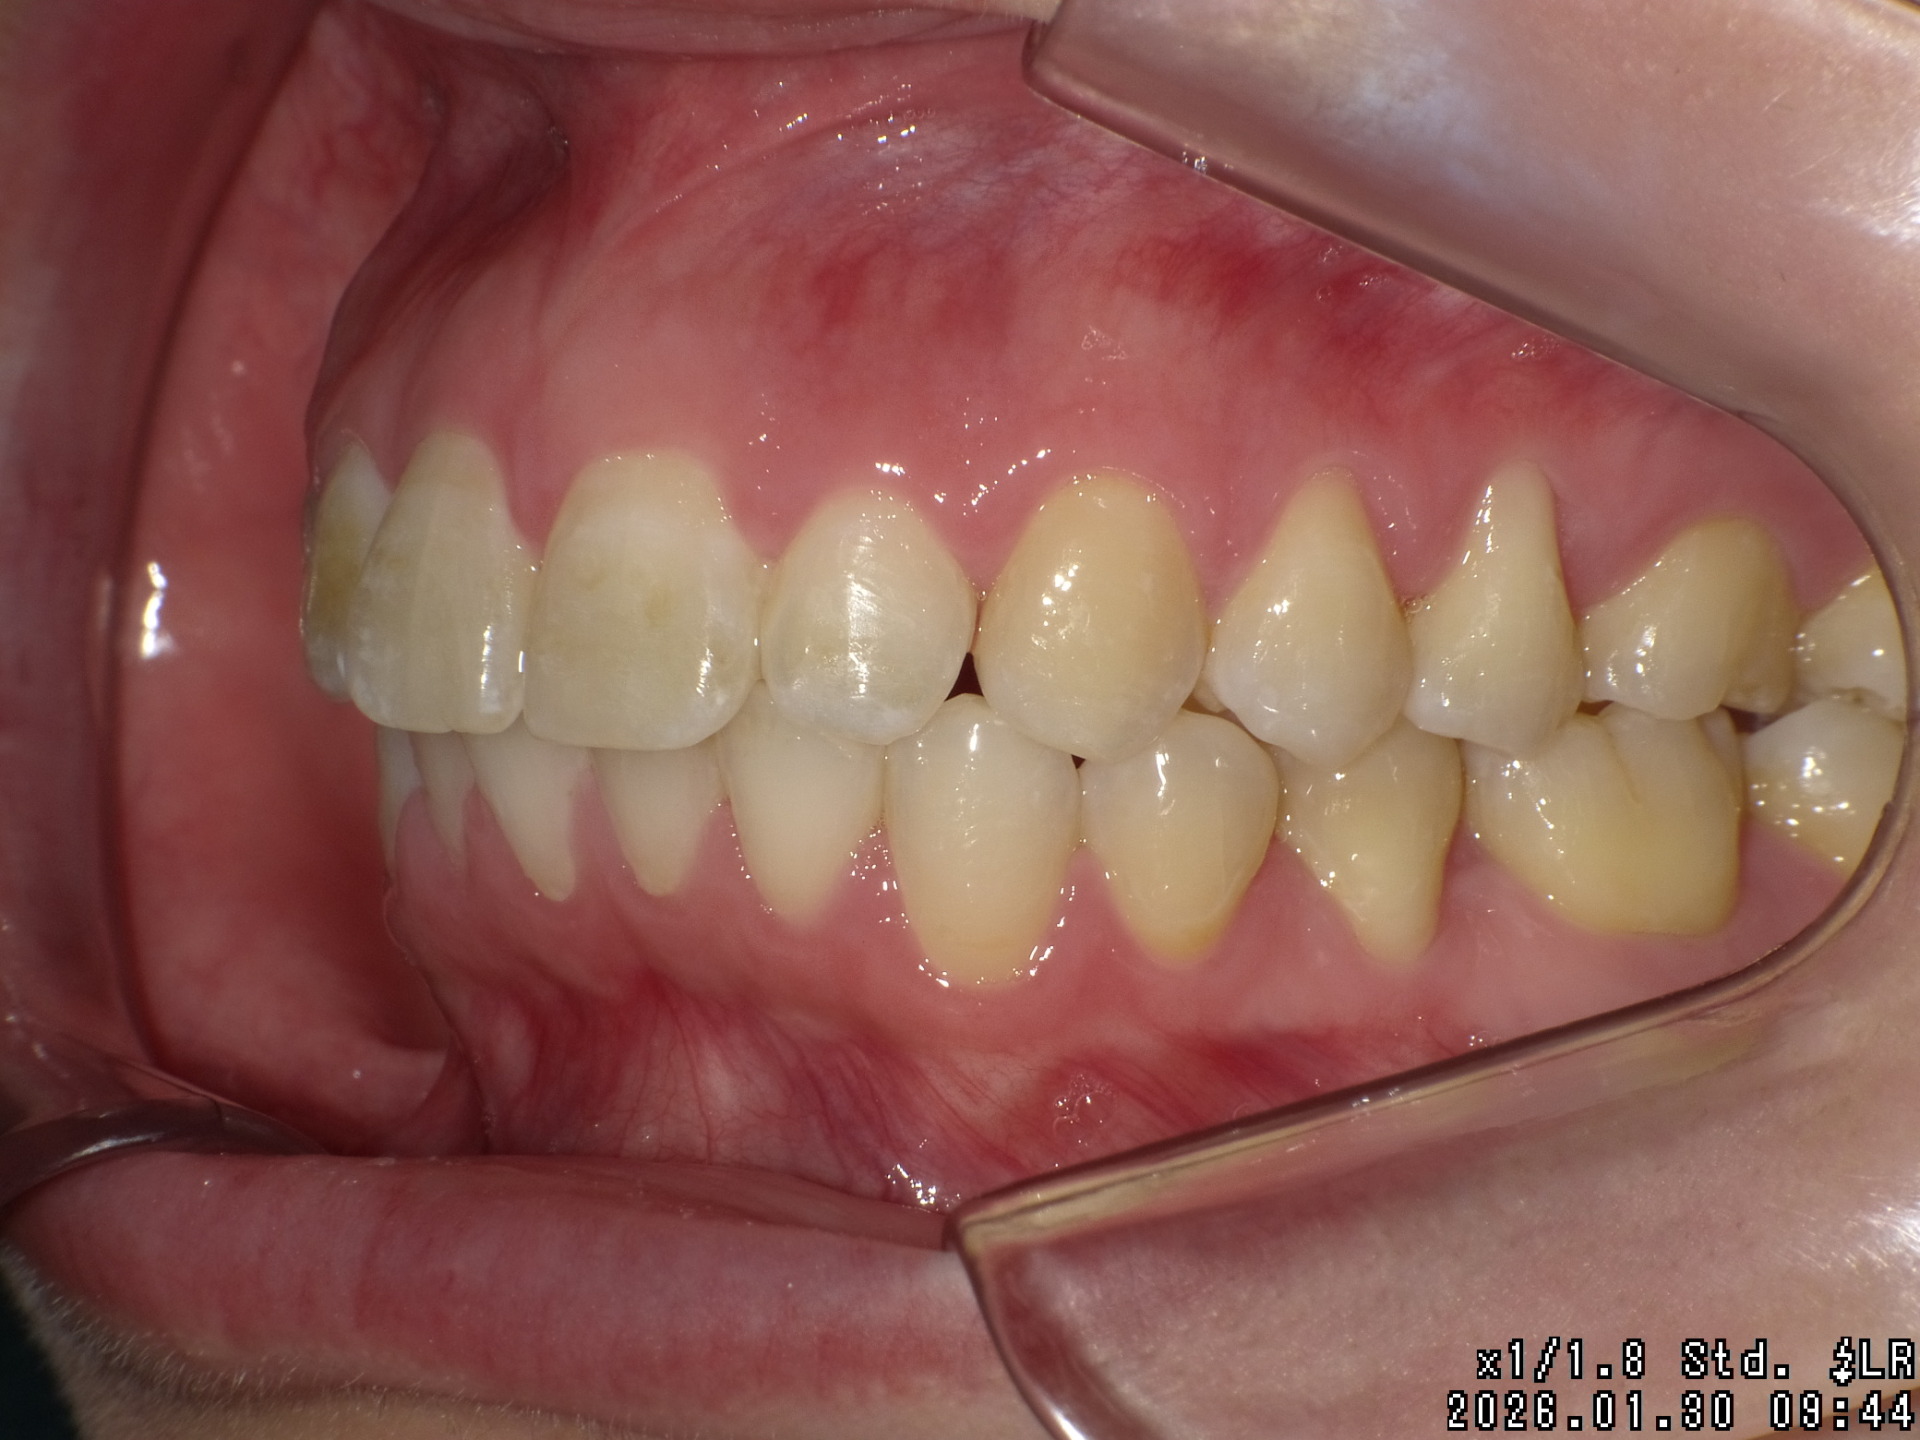

Before

| 症状 | 前歯が出ている |

|---|---|

| 通院時の 年齢 |

25才6ヶ月〜29才9ヶ月 |

| 通院回数 | 56回 |

| 通院目的 | 永久歯を抜かずに歯並びを治したい。 |

| 処置内容 | ディスタライザー・マルチブラケット装置 |

| 費用 | 基本料金 基本料金950,000円 (通院時4,400円の調整料を頂いていました。) ※過去の治療の料金ですので、現在とは異なります。現在は最高額1,240,000円(およそ治療期間4〜7年分)です。 |

| デメリット・院長コメント | 永久歯を抜かない治療のデメリットは、治療期間が長いことです。 ただし、その後の人生の長さを考えると、健全な小臼歯を2本または4本抜歯の矯正治療よりも、はるかにメリットがあるといえます。 また、アーチが小さくならないので、舌が後ろに押し込まれないためいびき防止につながり睡眠の質の向上にもつながります。 |